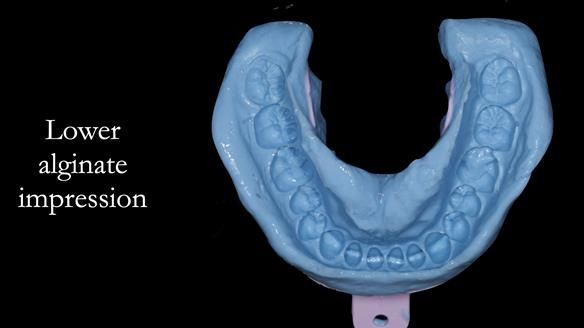

The clinical situation and treatment process is shown in detail below with photographs. I (Finlay Sutton) provided the clinical work and Rowan Garstang provided the technical work.